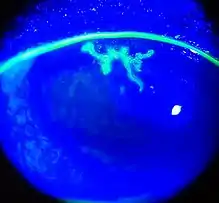

| Dendritic corneal ulcer after fluorescein staining | |

Dendritic ulcer (Epithelial keratitis)

This classic herpetic lesion consists of a linear branching corneal ulcer (dendritic ulcer). During eye exam the defect is examined after staining with fluorescein dye. The underlying cornea has minimal inflammation.

Patients with epithelial keratitis complain of foreign-body sensation, light sensitivity, redness and blurred vision.

Focal or diffuse reduction in corneal sensation develops following recurrent epithelial keratitis.